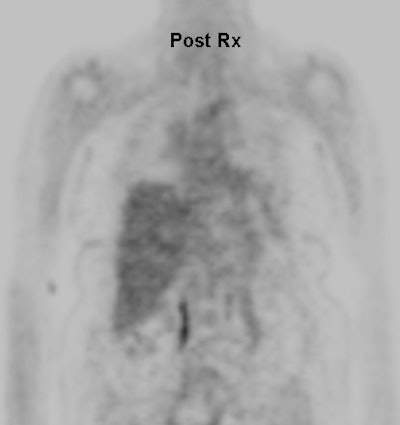

Cholangiocarcinoma: The patient below had a large cholangiocarcinoma. FDG PET imaging demonstrated markedly increased tracer uptake by the mass. There was no evidence of metastatic disease on PET imaging and the patient demonstrated a dramatic response to chemotherapy. |